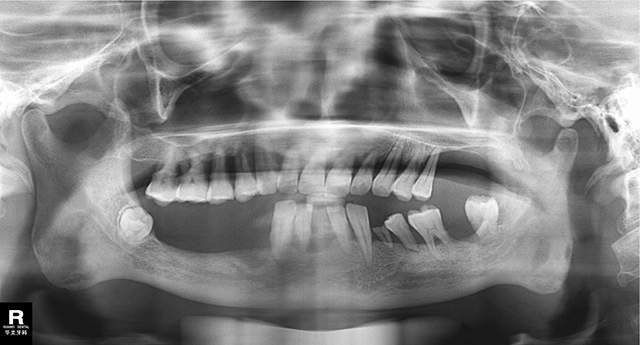

庄先生术前口腔情况

近期,庄先生来到华美牙科龙泉店进行咨询,该院医生再次为庄先生做了检查,发现他由于缺失牙的影响,上颌的牙槽骨已开始萎缩。鉴于1年前的下半口的成功,庄先生当场要求再做上半口的种立得快速种植牙。手术当天完成,当晚,庄先生就吃上了美食。目前,庄先生拥有了跟年轻时候一样的一口好牙。